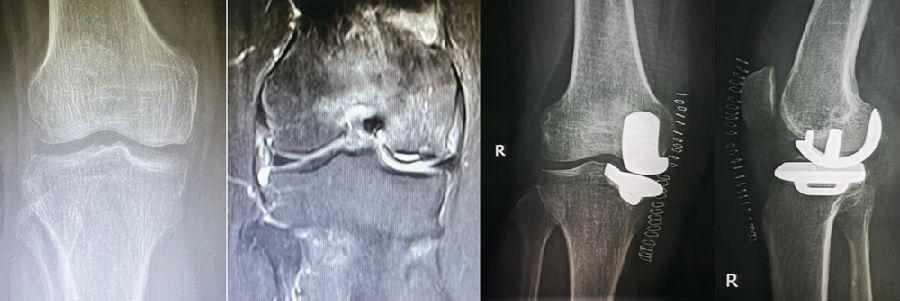

病例1:女,61岁,右膝关节诊断为Koshino Ⅲ期SONK,行右膝内侧单髁手术治疗。